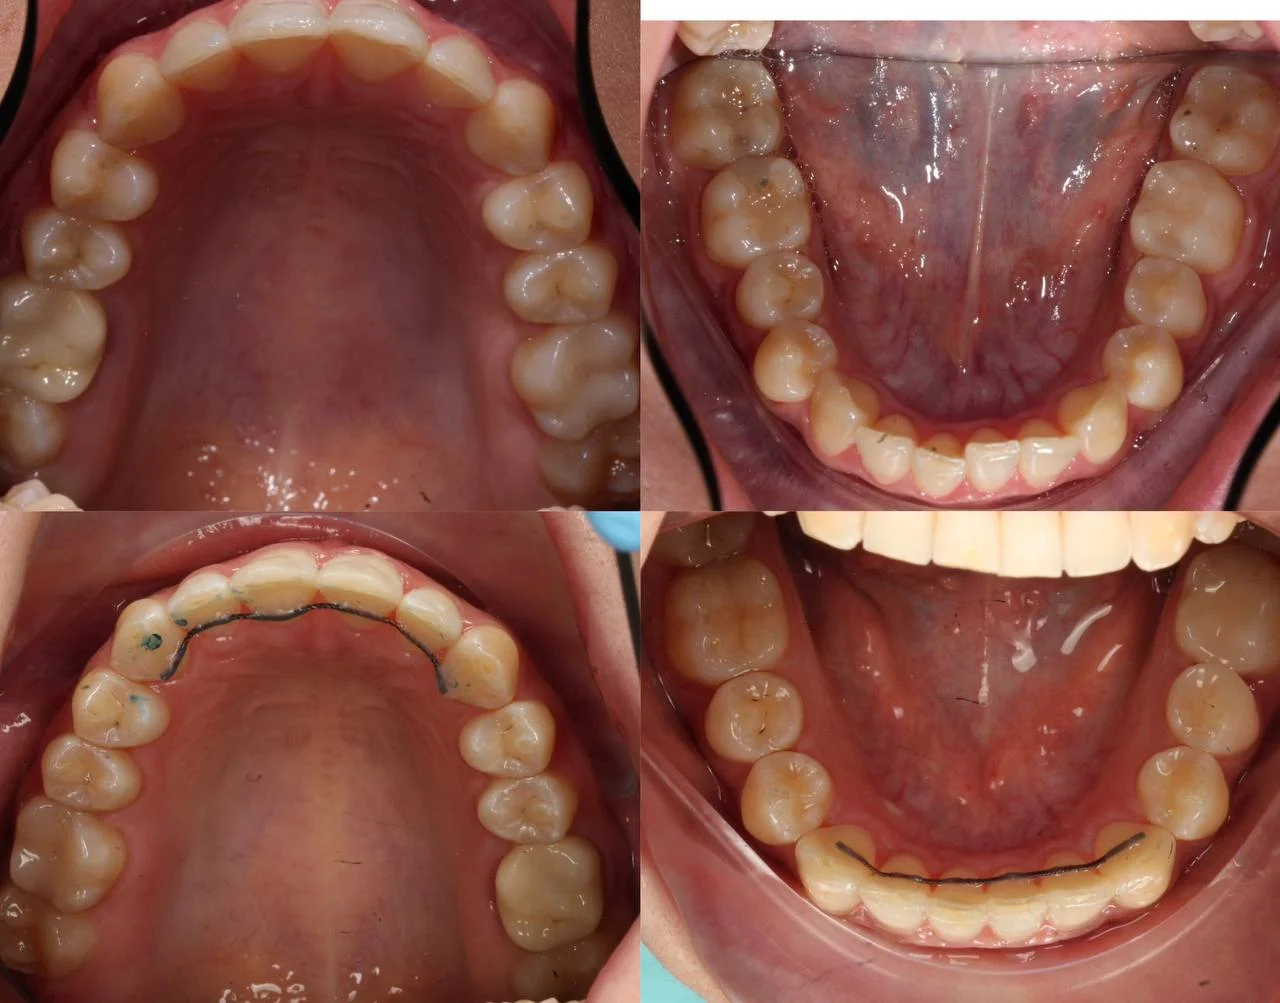

Прозрачные элайнеры Click на обе челюсти. Расширить зубные дуги, убрать скученность, выровнять линию смыкания. Основной набор — 32 капы. Срок — около 2 лет.

Лечение заняло 30 месяцев (август 2023 — февраль 2026). Понадобились три дополнительных набора: 30, 10 и 10 кап — итого 82 капы. Пациентка живёт за рубежом, приезжала на визиты — что иногда влияло на частоту контроля и сроки. На ретенцию приехала отдельно.

Решение: Поставили элайнеры Click на обе челюсти. Начали с 32 кап, но случай потребовал три дозаказа: 30, 10 и 10 кап — итого 82 капы за 30 месяцев. Количество дозаказов объясняется и сложностью случая (скученность плюс деформация кривой Шпее), и тем, что контрольные визиты были реже обычного из-за проживания за границей. Тем не менее результат достигнут: зубы ровные, смыкание в норме. На ретенцию пациентка приехала отдельно — зафиксировали ретейнеры на обе челюсти, сняли слепки для ретенционных кап.

Сложный случай: скученность на обеих челюстях плюс деформация кривой Шпее — жевательные зубы на разной высоте. Дополнительный вызов — пациентка живёт за рубежом, визиты реже, контроль сложнее. Три дозаказа — много, но каждый был обоснован: основной набор расширил дуги и убрал основную скученность, дозаказы последовательно довели смыкание до нормы. 82 капы за 30 месяцев — результат получен.